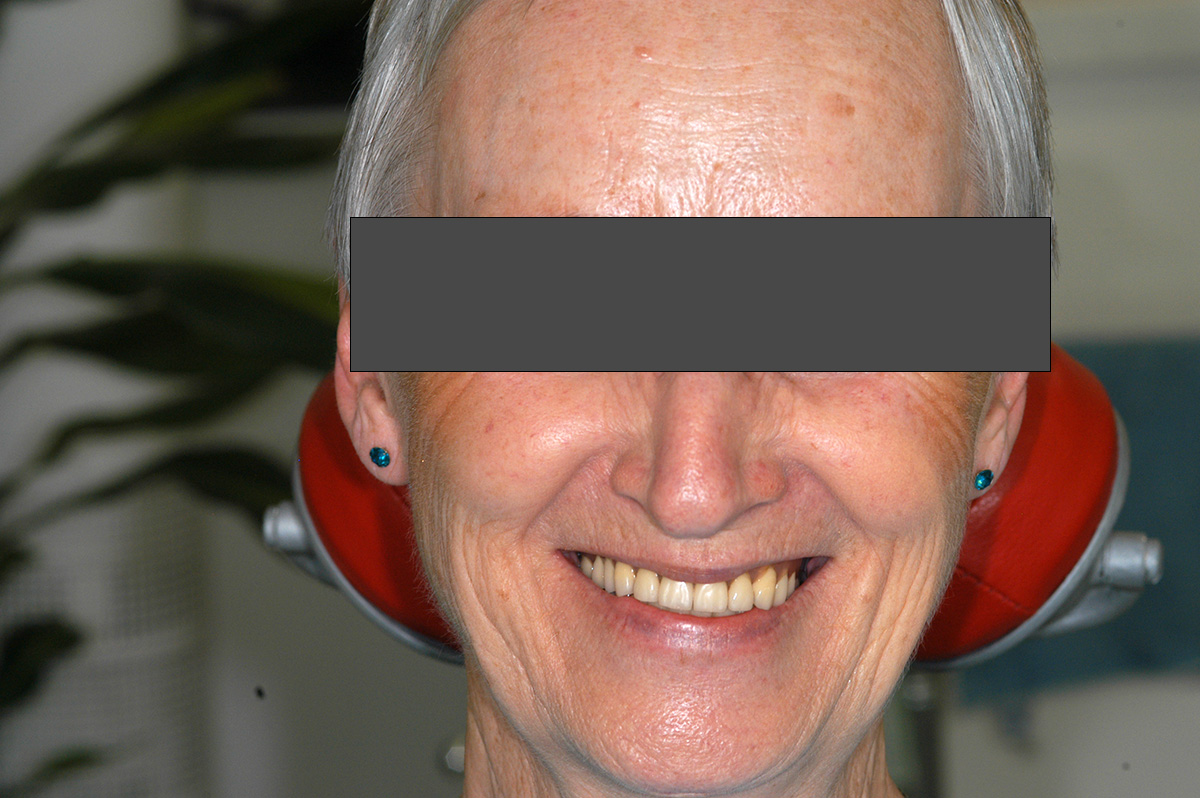

Vorher / Nachher

Beispiel 1